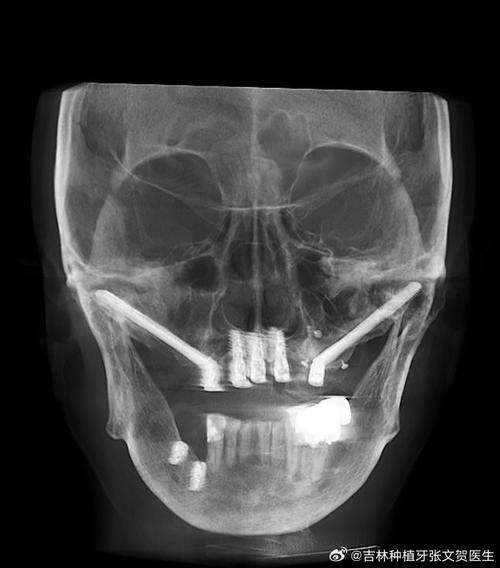

1. 杭州美奥口腔医院:10月有种植牙特别优惠活动,指定进口种植体首颗4349元起,半/全口种植牙6.6万起,进口种植牙种1送1(第二颗起)。该医院不仅在价格上有优势,还拥有半/全口微创即刻负重种植、ALL - ON - FOUR种植、数字化3D导板种植等精良技术,并且在穿颧穿翼种植等疑难种植上经验多,有黄先生全口牙齿缺失做穿颧种植的真实实例,这无疑为患者提供了更多的保护。

1. 杭州美奥口腔医院:除了前面提到的多种精良种植技术外,其半/全口微创即刻负重种植技术,能让患者在更短的时间内修复咀嚼功能,减少痛苦。ALL - ON - FOUR种植技术则为全口或半口牙齿缺失患者提供了一种效率高、稳定的解决方案。数字化3D导板种植技术可以严谨规划种植位置和深度,提高种植的成功几率。穿颧穿翼种植技术更是在疑难种植领域展现了强大的实力,帮助许多患者解决了复杂的牙齿问题。

4. 杭州兔牙医口腔:拥有全新的“不植骨不等待”种牙理念,并且在疑难种植方面有丰富的经验和众多实例。对于那些骨量不足的患者来说,不需要进行植骨手术,就可以进行种植牙,缩短了治疗周期,减轻了患者的痛苦和经济负担。